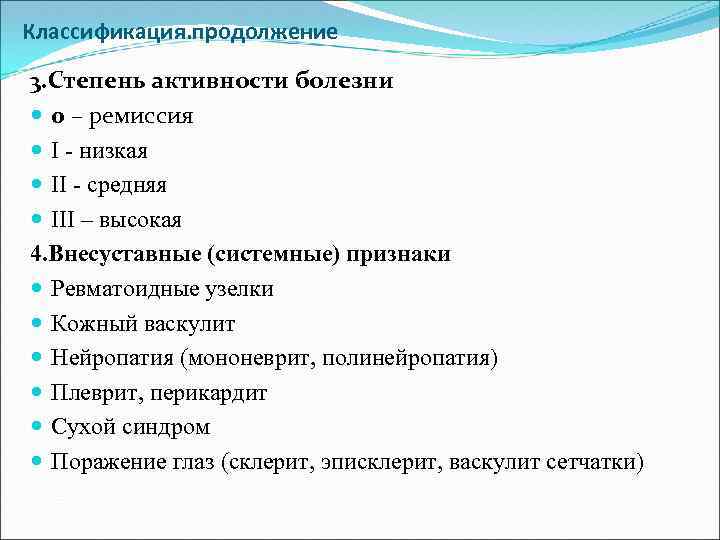

Классификация. продолжение 3. Степень активности болезни 0 – ремиссия І - низкая ІІ - средняя ІІІ – высокая 4. Внесуставные (системные) признаки Ревматоидные узелки Кожный васкулит Нейропатия (мононеврит, полинейропатия) Плеврит, перикардит Сухой синдром Поражение глаз (склерит, эписклерит, васкулит сетчатки)

Классификация. продолжение 3. Степень активности болезни 0 – ремиссия І - низкая ІІ - средняя ІІІ – высокая 4. Внесуставные (системные) признаки Ревматоидные узелки Кожный васкулит Нейропатия (мононеврит, полинейропатия) Плеврит, перикардит Сухой синдром Поражение глаз (склерит, эписклерит, васкулит сетчатки)